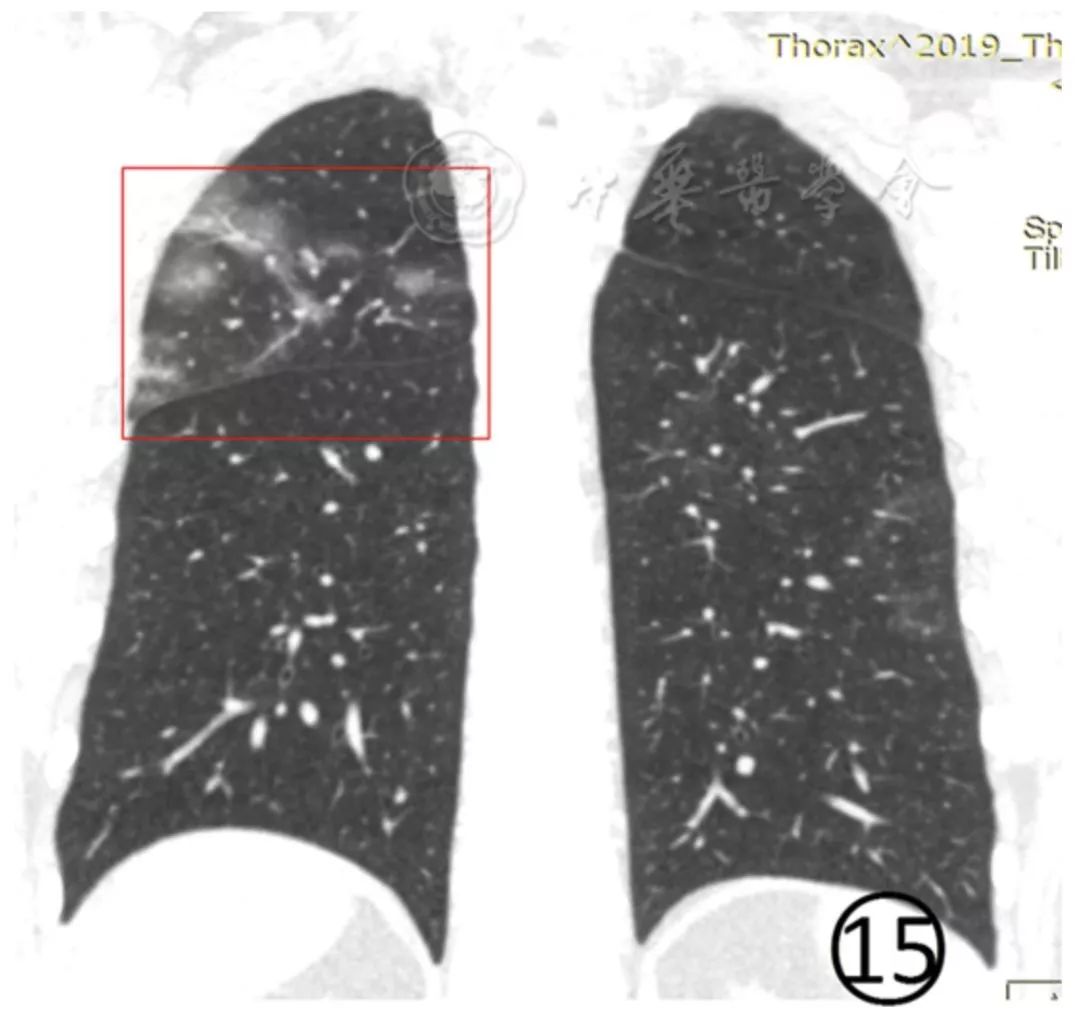

图12 男,55岁。CT平扫肺窗显示左肺上、下叶见磨玻璃阴影,左侧斜裂胸膜轻度增厚、模糊(红色框内)。右肺下叶背段之亚段性磨玻璃阴影内细支气管柱状增粗(↑),胸膜下局部实变并有小叶间隔增厚、移位。部分病变呈亚段性分布的大片磨玻璃阴影,病变内小血管增多,类似于细网格状阴影或"铺路石征" (图13,图14)。部分磨玻璃阴影有"反晕征" (图15)。

图15 男,38岁。CT平扫肺窗显示右上肺胸膜下有"反晕征" ,肺内有多发的小斑片状磨玻璃阴影